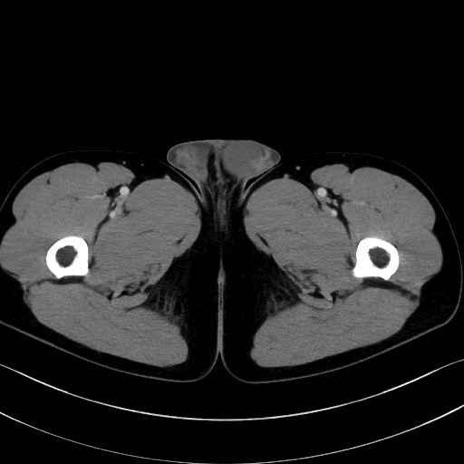

精嚢(seminal vesicle)のCT画像における解剖

症例

【症例】20歳代 男性 スクリーニング